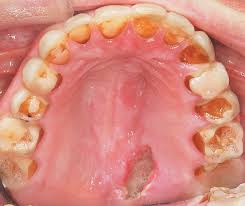

- Язвы в ротовой полости и проблемы с зубами, вызванные не только недостатком кальция, но и вредным воздействием желудочного сока на зубную эмаль при рвоте (кариес).

Последствиями в области ротовой полости, возникающими вследствие частой рвоты, является кариес и парадонтит. Помимо этого систематический вызов рвотного рефлекса может привести к охриплости голоса, повреждению слизистых оболочек верхних дыхательных путей, пищевода и желудка.

Частый прием слабительных и мочегонных средств, как правило, сопровождается обменными нарушениями — снижается уровень калия и хлора в сыворотке крови. А это, в свою очередь, может приводить к нарушению ритма сердечной деятельности (аритмии) вплоть до внезапной остановки сердца, общей слабости, сонливости. Помимо этого может наблюдаться снижение содержания кальция в костях, зубной ткани.

Постоянное выведение пищи с рвотой становится причиной хронического раздражения слизистого горла и ротовой полости, что соответственно вызывает фарингиты, стоматит, кариес.